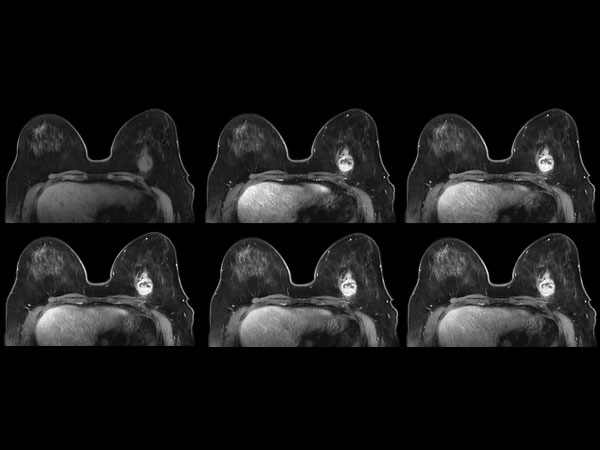

57 year old female with a new diagnosis of Ca. Sample obtained by US biopsy: Invasive Ductal Ca, grade 3. MR requested to aid in determining treatment.

Dynamic axial eTHRIVE